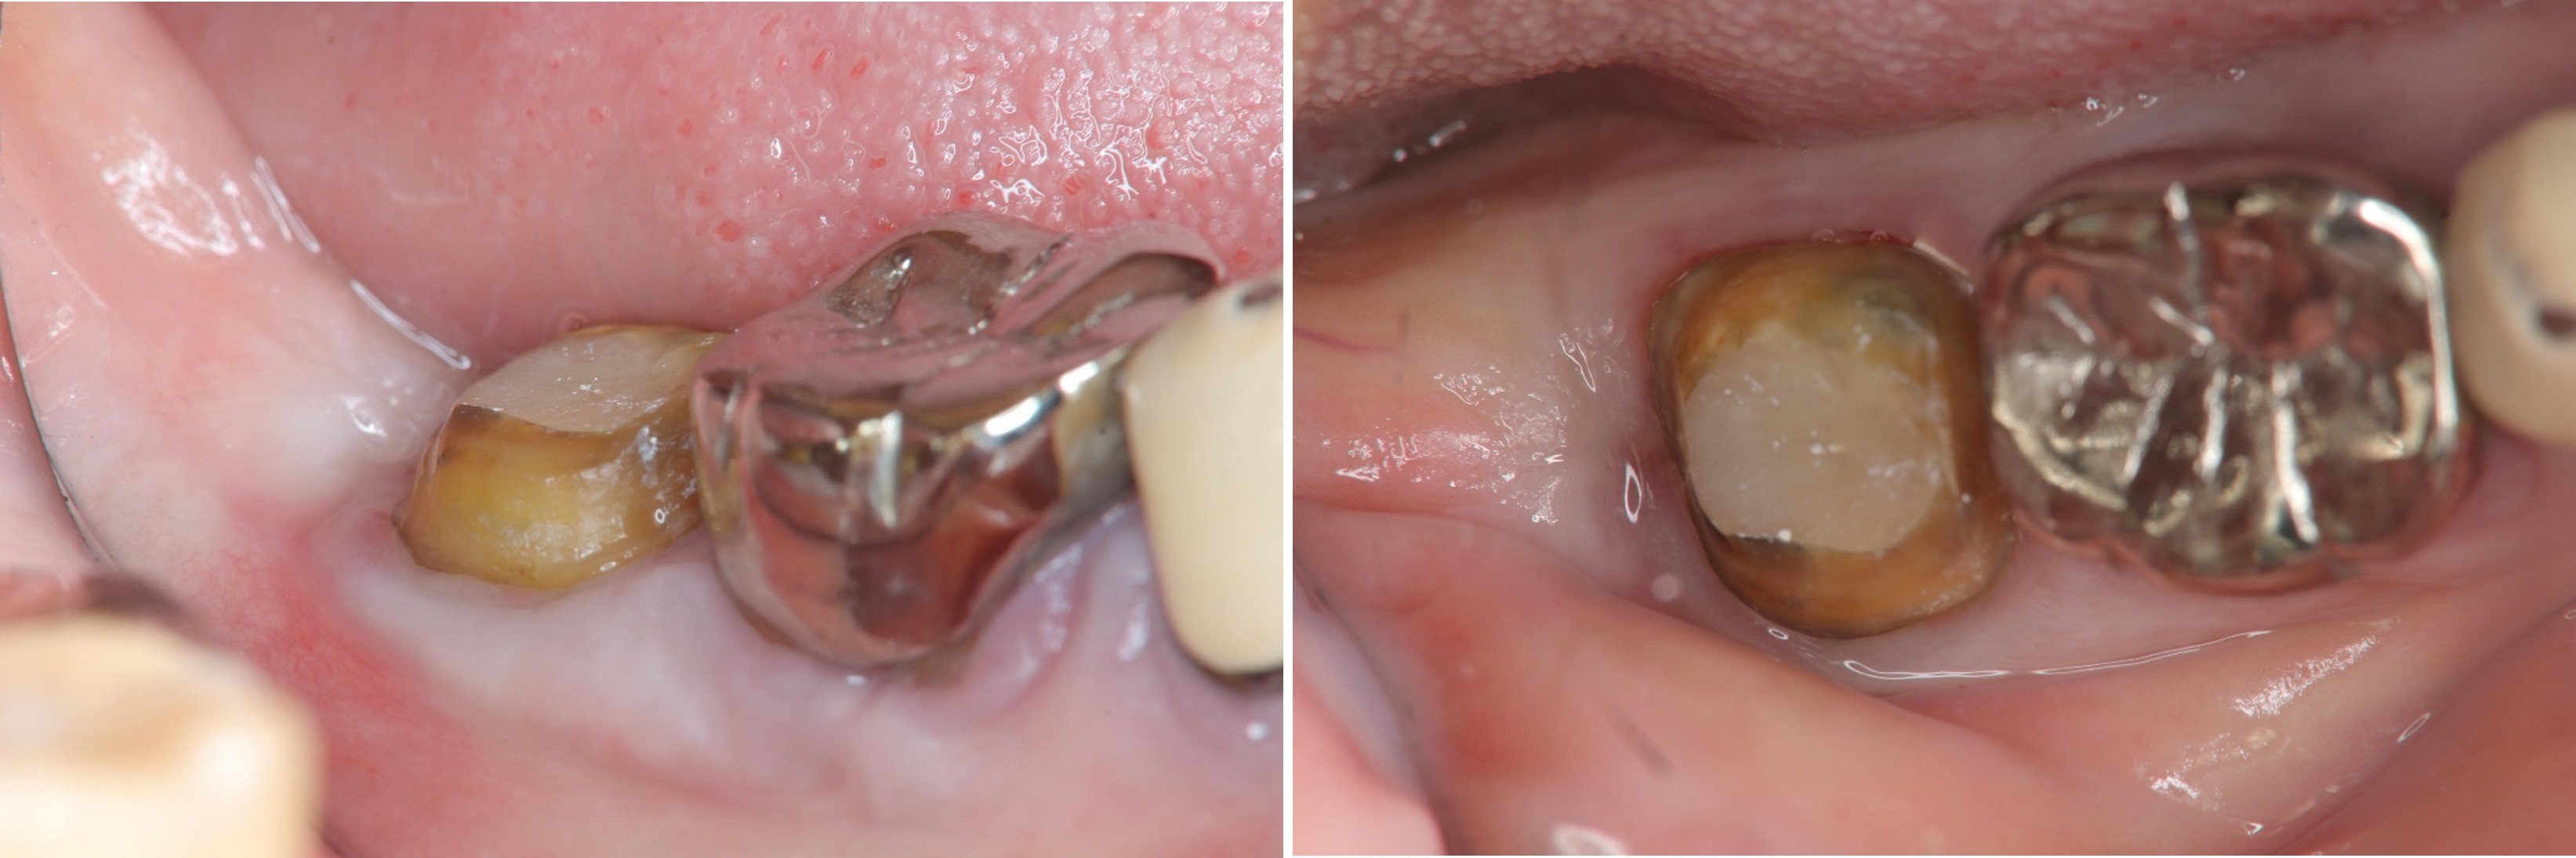

6週牙齦癒合良好

取面弓,上咬合器

製作固定假牙

因受力考量,製作金屬燒付瓷牙

術前、術後比較